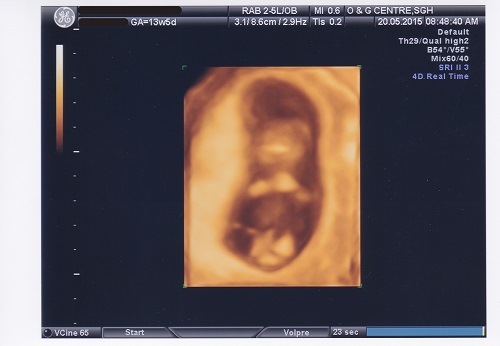

*Throwback post to week 12*

Oh my, how you’ve grown. From just a static jellybean with a pumping heart, you can now move your tiny hands and feet!

I was so relieved to see you alive and well. Daddy was also surprised to see you bounce and slide around. Our only wish is for you to grow up strong, healthy and happy. Never forget that!